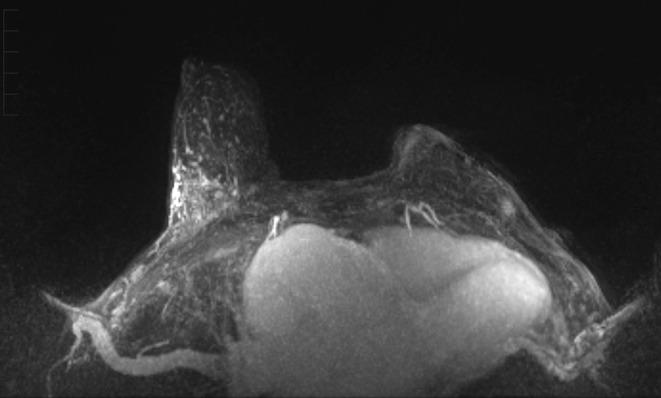

Pleomorphic Adenoma in the Setting of Triple-Negative Breast Cancer: A Case Report.

We report a case of a patient-detected breast mass that revealed invasive carcinoma adjacent to a pleomorphic adenoma, which was treated with wide local excision. This case report highlights the importance of careful pathologic evaluation to guide appropriate local and systemic therapy and avoid the potentially harmful effects of overtreatment.